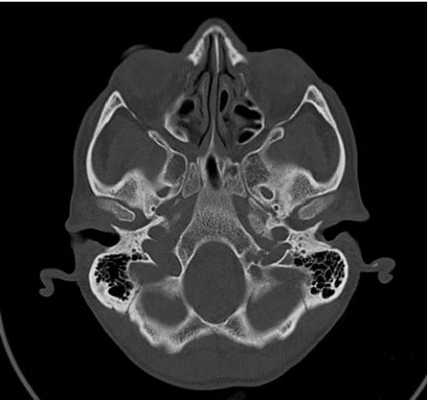

Снимок КТ основания черепа

Методика выполнения КТ основания черепа